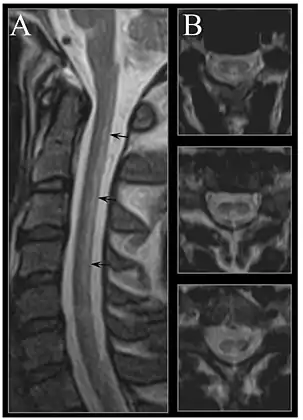

Early changes include a spongiform state of neural tissue, along with edema of fibers and deficiency of tissue. The myelin decays, along with axial fiber. In later phases, fibric sclerosis of nervous tissues occurs. Those changes occur in dorsal parts of the spinal cord and to pyramidal tracts in lateral cords and is called subacute combined degeneration of spinal cord.[43] Pathological changes can be noticed as well in the posterior roots of the cord and, to lesser extent, in peripheral nerves.

MRI of the brain may show periventricular white matter abnormalities. MRI of the spinal cord may show linear hyperintensity in the posterior portion of the cervical tract of the spinal cord, with selective involvement of the posterior columns.